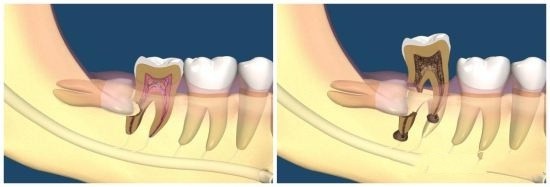

智齿是最后才生长的牙齿,当它在牙槽骨准备萌出时,却发现其他牙齿已把能占用的地方全占了——它已经没位置了!

智齿为了长出来,只能“自私”地顶坏前面的牙齿,这也是智齿会引起牙疼、牙龈发炎等问题的原因。

(智齿引起牙疼、牙龈发炎等问题)

讲到这里,你应该就明白我上面的话了。

但凡位置不正,别管属于专业术语中的哪一种类型,都存在萌出顶坏牙齿的风险,建议拔除。

尤其是那些“蠢蠢欲动”的智齿,已经引起了牙疼、牙龈发炎等情况,哪怕吃点消炎药将炎症又下去了,后面也会反复发作,并且一次比一次疼,一次比一次严重。